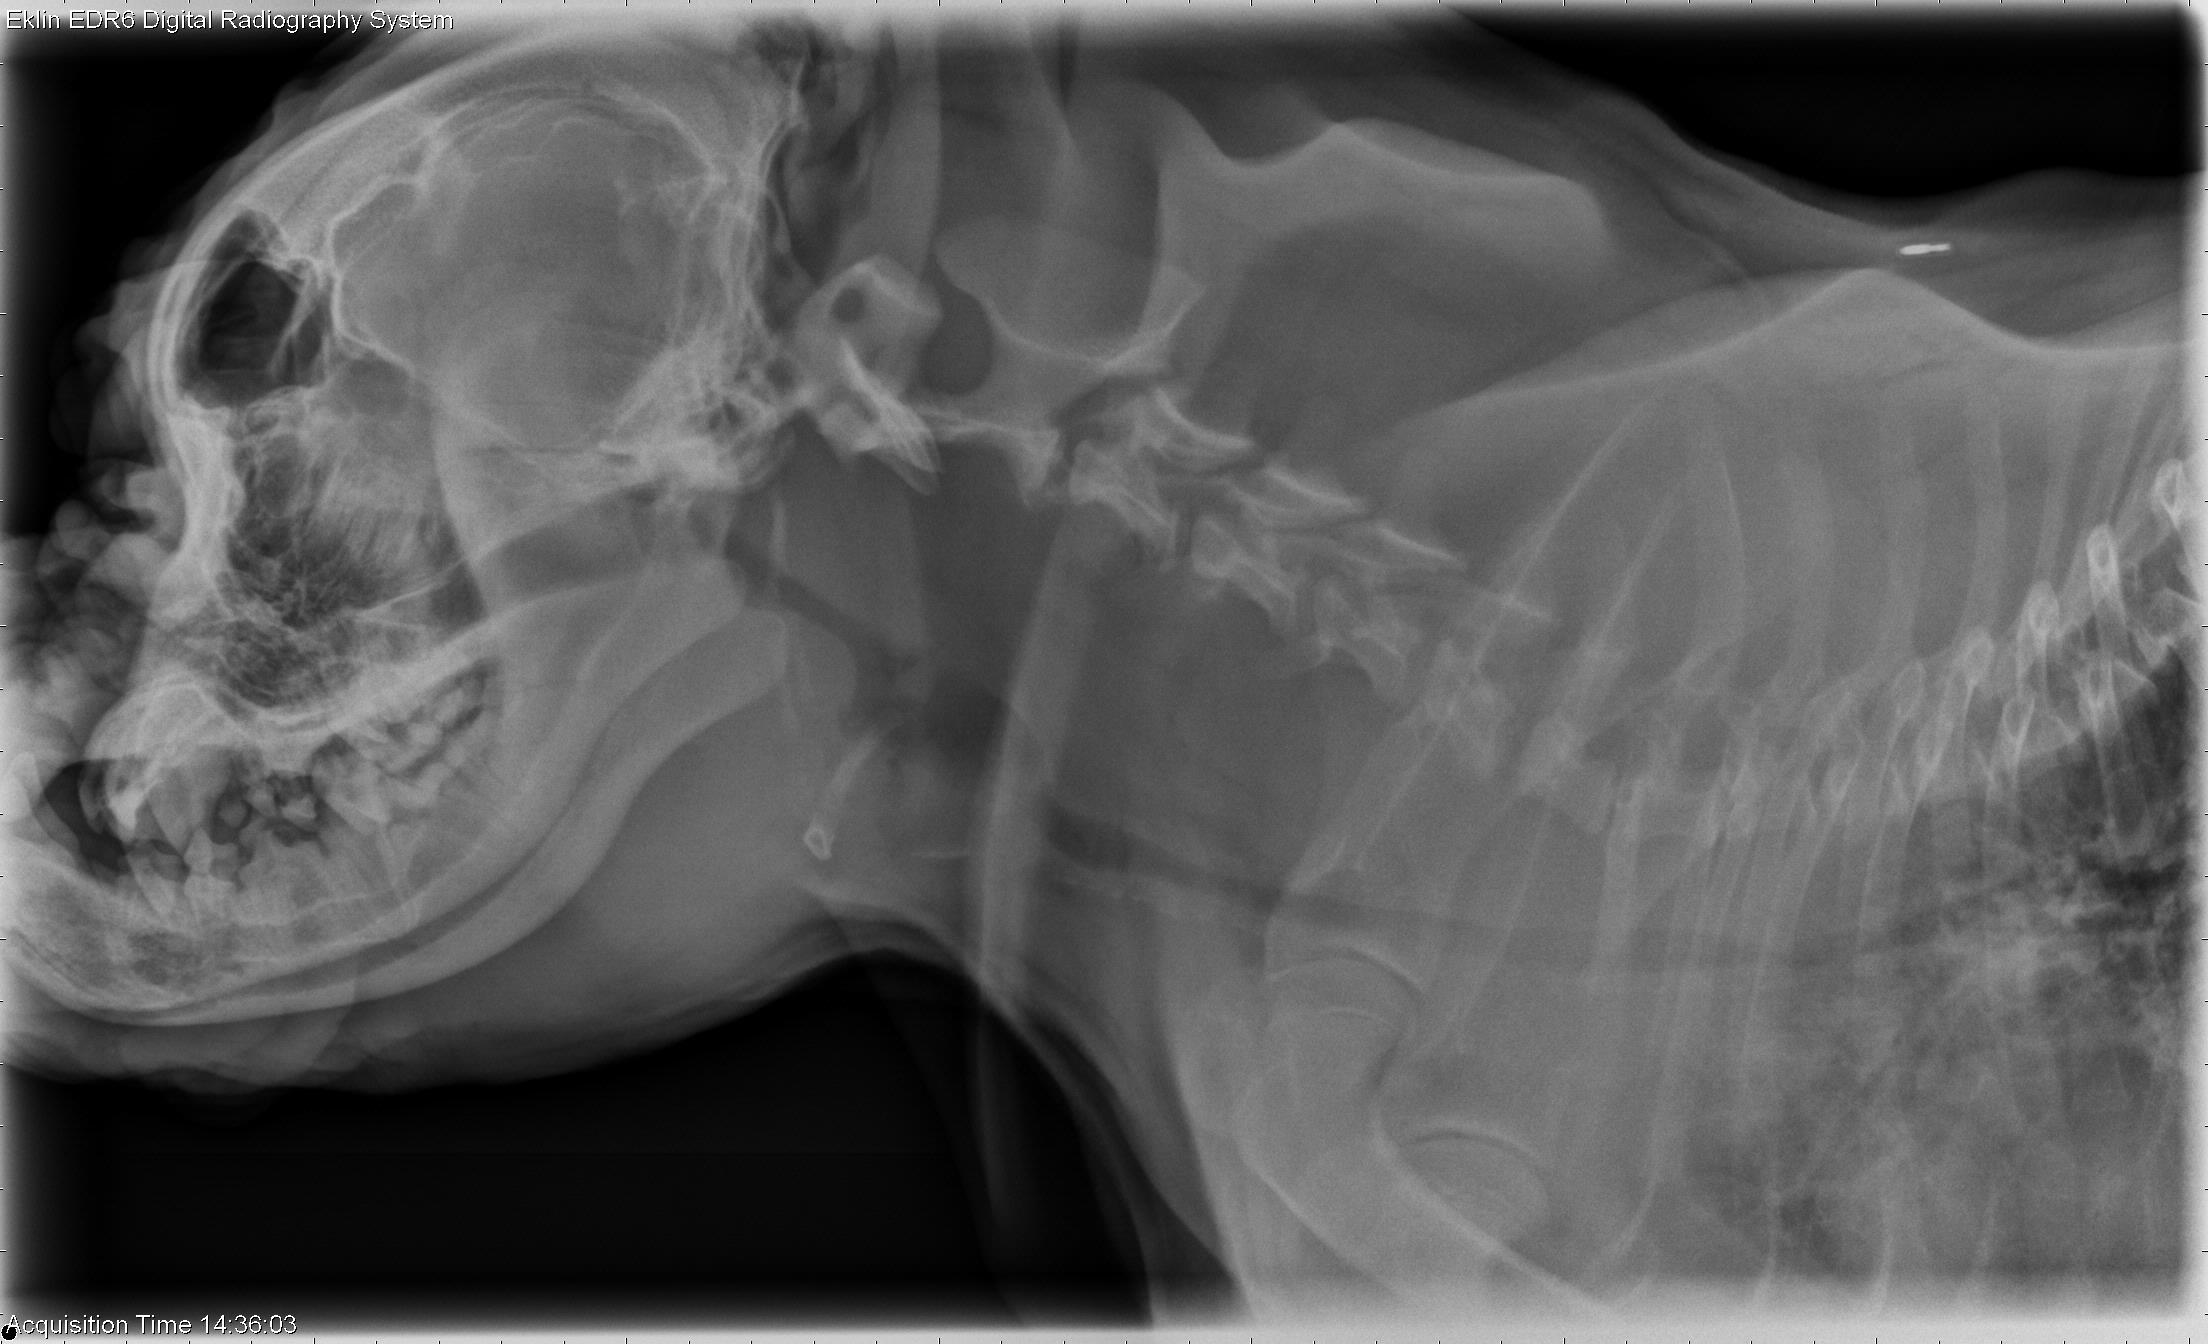

Dog Face Xray . Tape is applied behind the maxillary canine teeth to pull the nose 10° to 15° cranially (figure 6). Radiography of specific areas requires close attention. The patient’s nose should be pointing upward. After you have scanned the whole radiograph look very closely for subtle changes. The anatomy of the skull and nasofacial area of the dog and cat is complex, with cavities, sinuses, mandible, maxilla, dental arcades, and cranial cavity. There is a lot veterinarians can learn about a dog’s health through imaging.